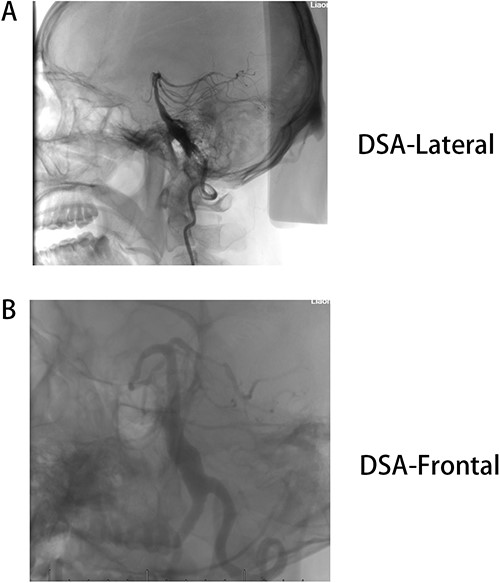

Male, AA, 44 years old, admitted in July 2022 with recurrent pain on the left side of the maxillofacial region for ~1 year. In the last 6 months, the dose of carbamazepine was increased to 300 mg three times daily, but the control of facial pain was still unsatisfactory, so the patient and his family numbers requested to be hospitalized for surgery. The patient had a history of hypertension for ~15 years. The maximum blood pressure was ~200/120 mmHg. The nifedipine controlled-release tablet was used to control his blood pressure by 30 mg daily, which is maintained at ~140/80 mmHg. The neurological examination on admission was unremarkable. TN was assessed as grade V according to the Bar row Neurological Institute classification. Magnetic Resonance Imaging (MRI) of the head suggests small ischemic focus in the pons and cerebellum; marked extending of the basilar artery (Fig. 1A–C). To clarify the etiology, doppler ultrasound of the carotid and vertebral arteries bilaterally revealed no atheromatous plaque or hemodynamics abnormalities. An electrocardiogram and cardiac function and cardiac ultrasound were performed. The results were normal. Biochemical tests for blood cell count, liver function, kidney function, and glucose test revealed no abnormalities. The Digital subtraction angiography (DSA) was given to the patient (Fig. 2A and B). Antiplatelet aggregation therapy with a combination of clopidogrel and aspirin was used before operation. The DSA displayed the VBD, the VBD was length 2.5 cm and width 9 mm, its path was tortuous and deviated to the left. Normal blood flow in the middle venous phase of the imaging was normal. Stent-assisted interventional embolization was chosen. A suitable coil was selected to form basket by EV3 (20 mm*50 cm, Medtronic, USA) and the stent catheter was withdrawn and repositioned through the coil into the right posterior cerebral artery. Release stent 1: LEO (5.5 mm*60 mm, LEO, USA), then choose the appropriate ring (14 mm*30 cm, 13 mm*30 cm, 12 mm*30 cm, 10 mm*30 cm, Taijie Weiye, China) to occlude the dilated artery (Fig. 3A). Postoperatively, we scanned the Computed Tomography (CT) (Fig. 3A), the TN was completely relieved, but there was residual left-sided facial palsy with a House-Brackmann grade IV and a grade III right limb muscle strength. Systematic treatment was operated at the rehabilitation unit, once the condition was stabilized. At 3 months post-operative follow-up the patient showed significant improvement in muscle strength in the right limb, with muscle strength grade V− and significant improvement in facial palsy, which was graded House-Brackmann grade II.

(A) MRI 3D-TOF(3 digital- time of flight), (B) MRI T2, C:MRI T1. Basilar trunk dilation up to 9 mm of diameter deviated path to the left side responsible of medulla compression.